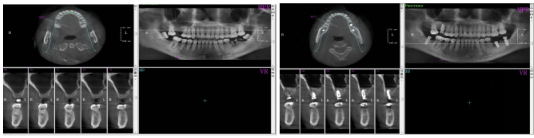

图1 种植术前术后口内照片

该患者因上颌多颗后牙缺失数年,伴随牙槽骨严重吸收、上颌窦底骨量严重不足,同时口内存在残根、阻生智齿,曾被判定为常规种植方案无法实施,种植难度极高。为最大限度减少患者创伤与往返就诊负担,阿坝州人民医院口腔科团队术前通过口腔CBCT完成全维度解剖结构评估,精准测算骨量数据,量身定制了“一站式”微创种植方案。

得益于上述核心技术的综合应用,手术全程术野清晰,未出现上颌窦黏膜穿孔等并发症,4颗种植体均达到理想的初期稳定性。相较于传统方案需3-4次手术、近半年的治疗周期,本次一站式手术不仅突破了患者“无种植条件”的限制,更极大降低了手术创伤,术后患者反应轻微,恢复情况良好,真正实现了微创、高效、安全的种植修复。